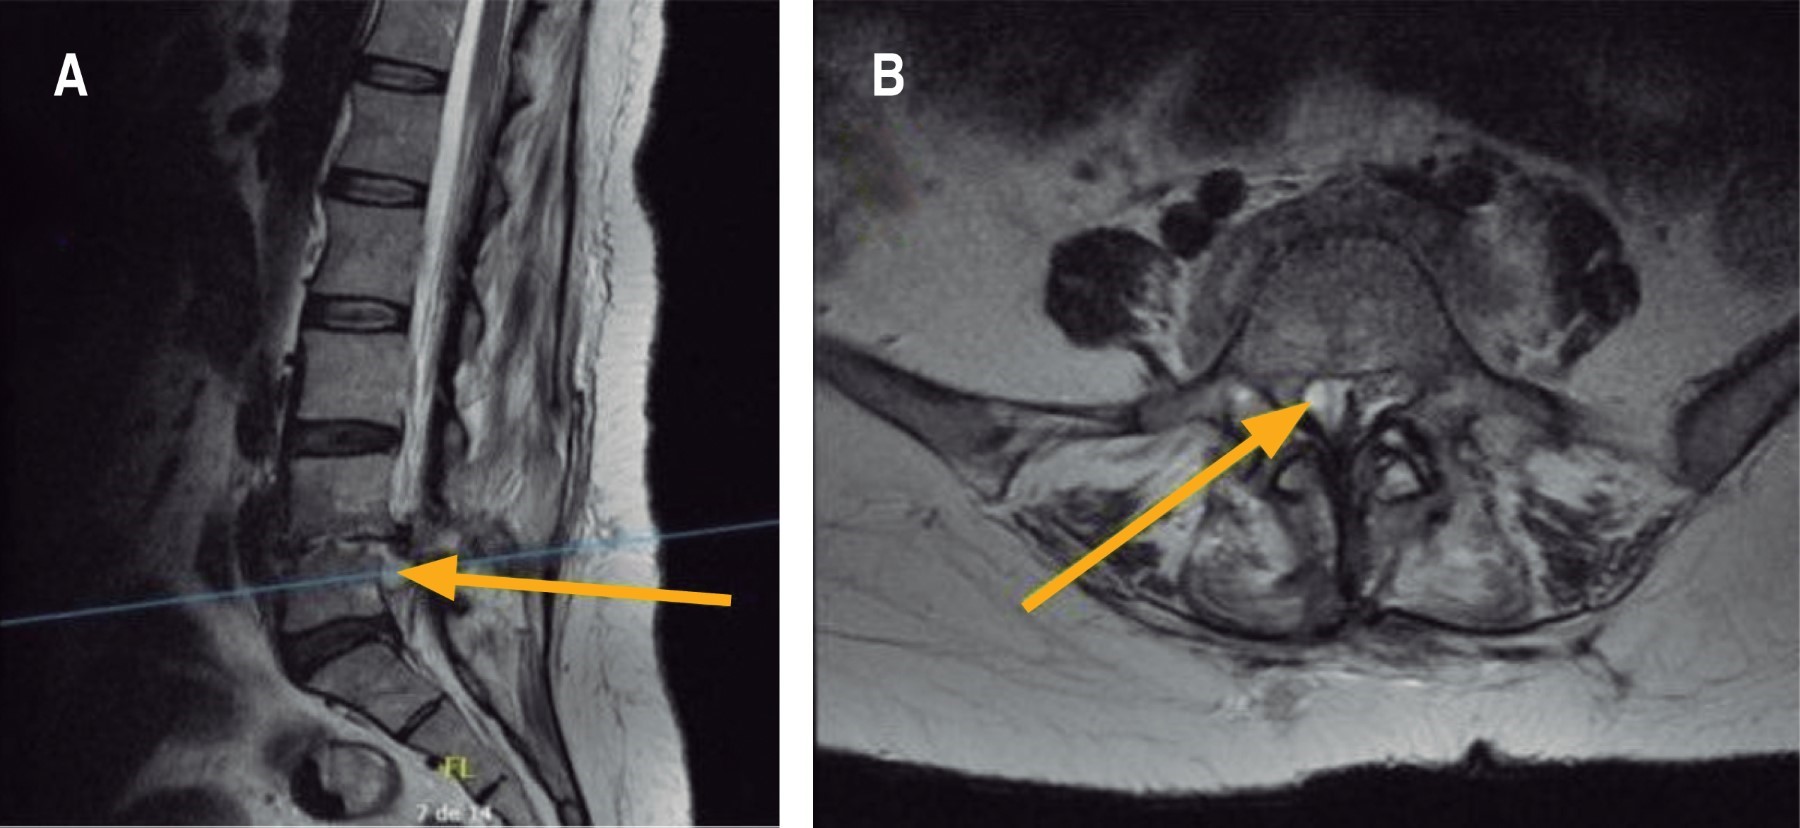

Figura 2